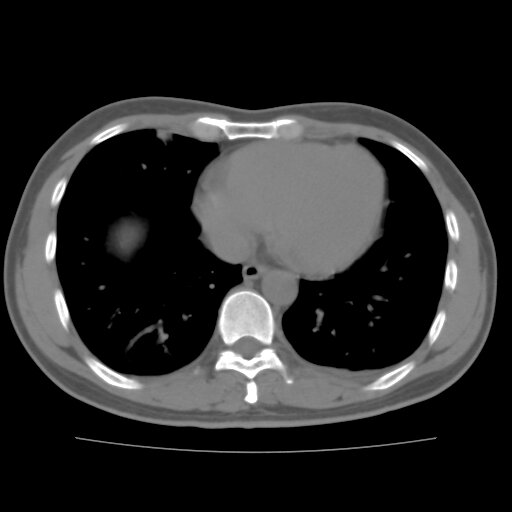

左侧胸痛,无其他病史

炎性假瘤

考虑肺内炎性肉芽肿,少量胸水。

转移瘤

考虑两肺感染性病变;建议抗炎治疗后复查。

暂考虑两肺感染性病变,左侧少量胸水;建议抗炎治疗后复查

首先考虑双肺感染性病变,左侧少量胸水,见过类似病例,抗炎后都吸收了

右侧胸膜下多发小结节——支持考虑:炎性假瘤!

警惕转移灶